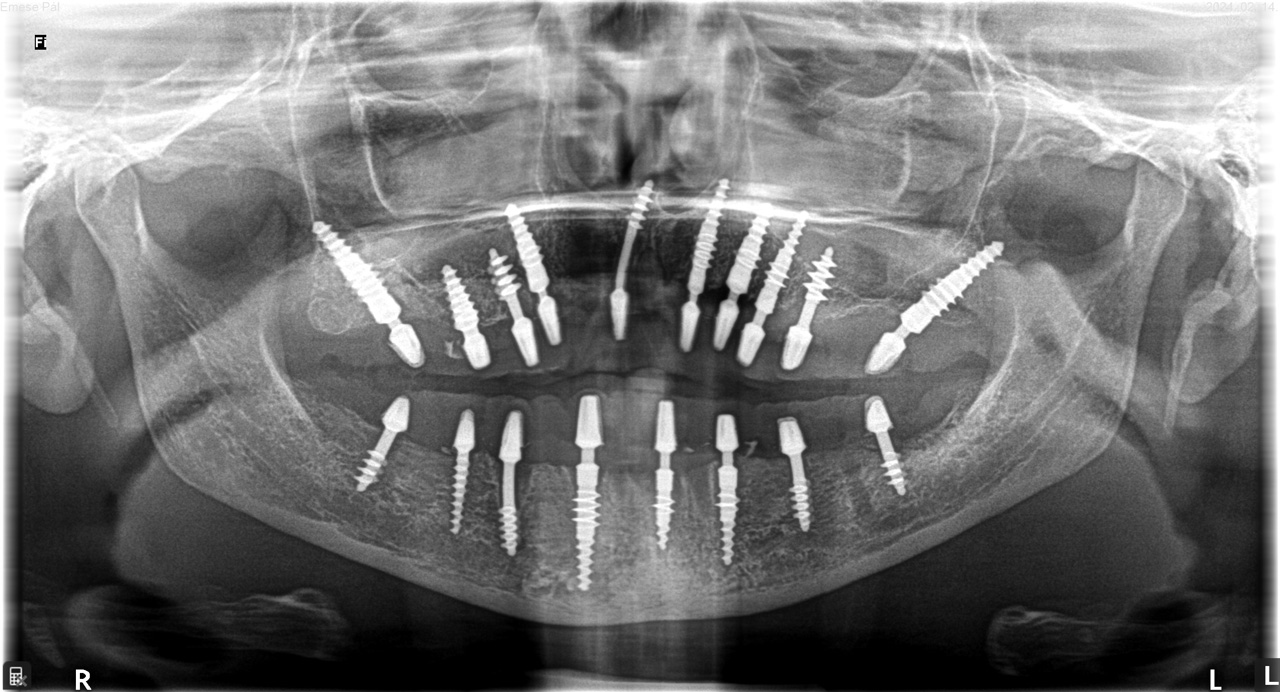

Teljes fogatlanság helyreállítása 2 nap alatt

Teljes fogatlanság helyreállítása 2 nap alatt azonnal terhelhető svájci IHDE implantátumokkal és PMMA műanyag hidakkal. Intraorális szkennerrel vettünk lenyomatot az implantáció után, és erre a digitális mintára készítette el a fogtechnika a hidak digitális tervezését, majd faragta ki műanyagból. Ezt a gyors munkát az azonnal terhelhető implantátumok és a digitális lenyomat, tervezés segítségével tudtuk megcsinálni mindössze 2 nap alatt. Dr. Kelemen Péter és a Symbion Fogtechnika munkája.